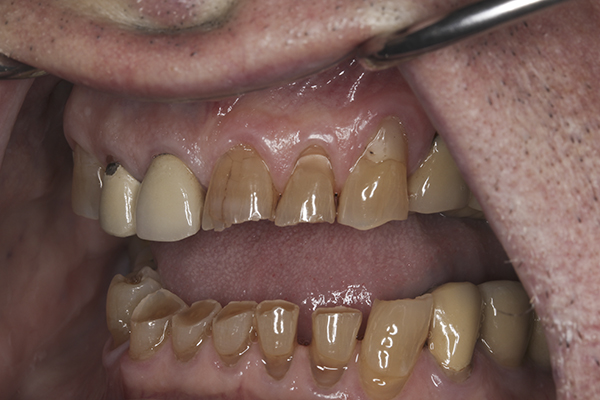

(7.) Preoperative anterior, open view. Note the significant amount of wear, erosion, and abfraction lesions.

Figure 7

(10.) Preoperative anterior, closed view. Note the end-to-end occlusion of the anterior teeth and the wear on the incisors and centrals resulting in no anterior or canine guidance.

Figure 10